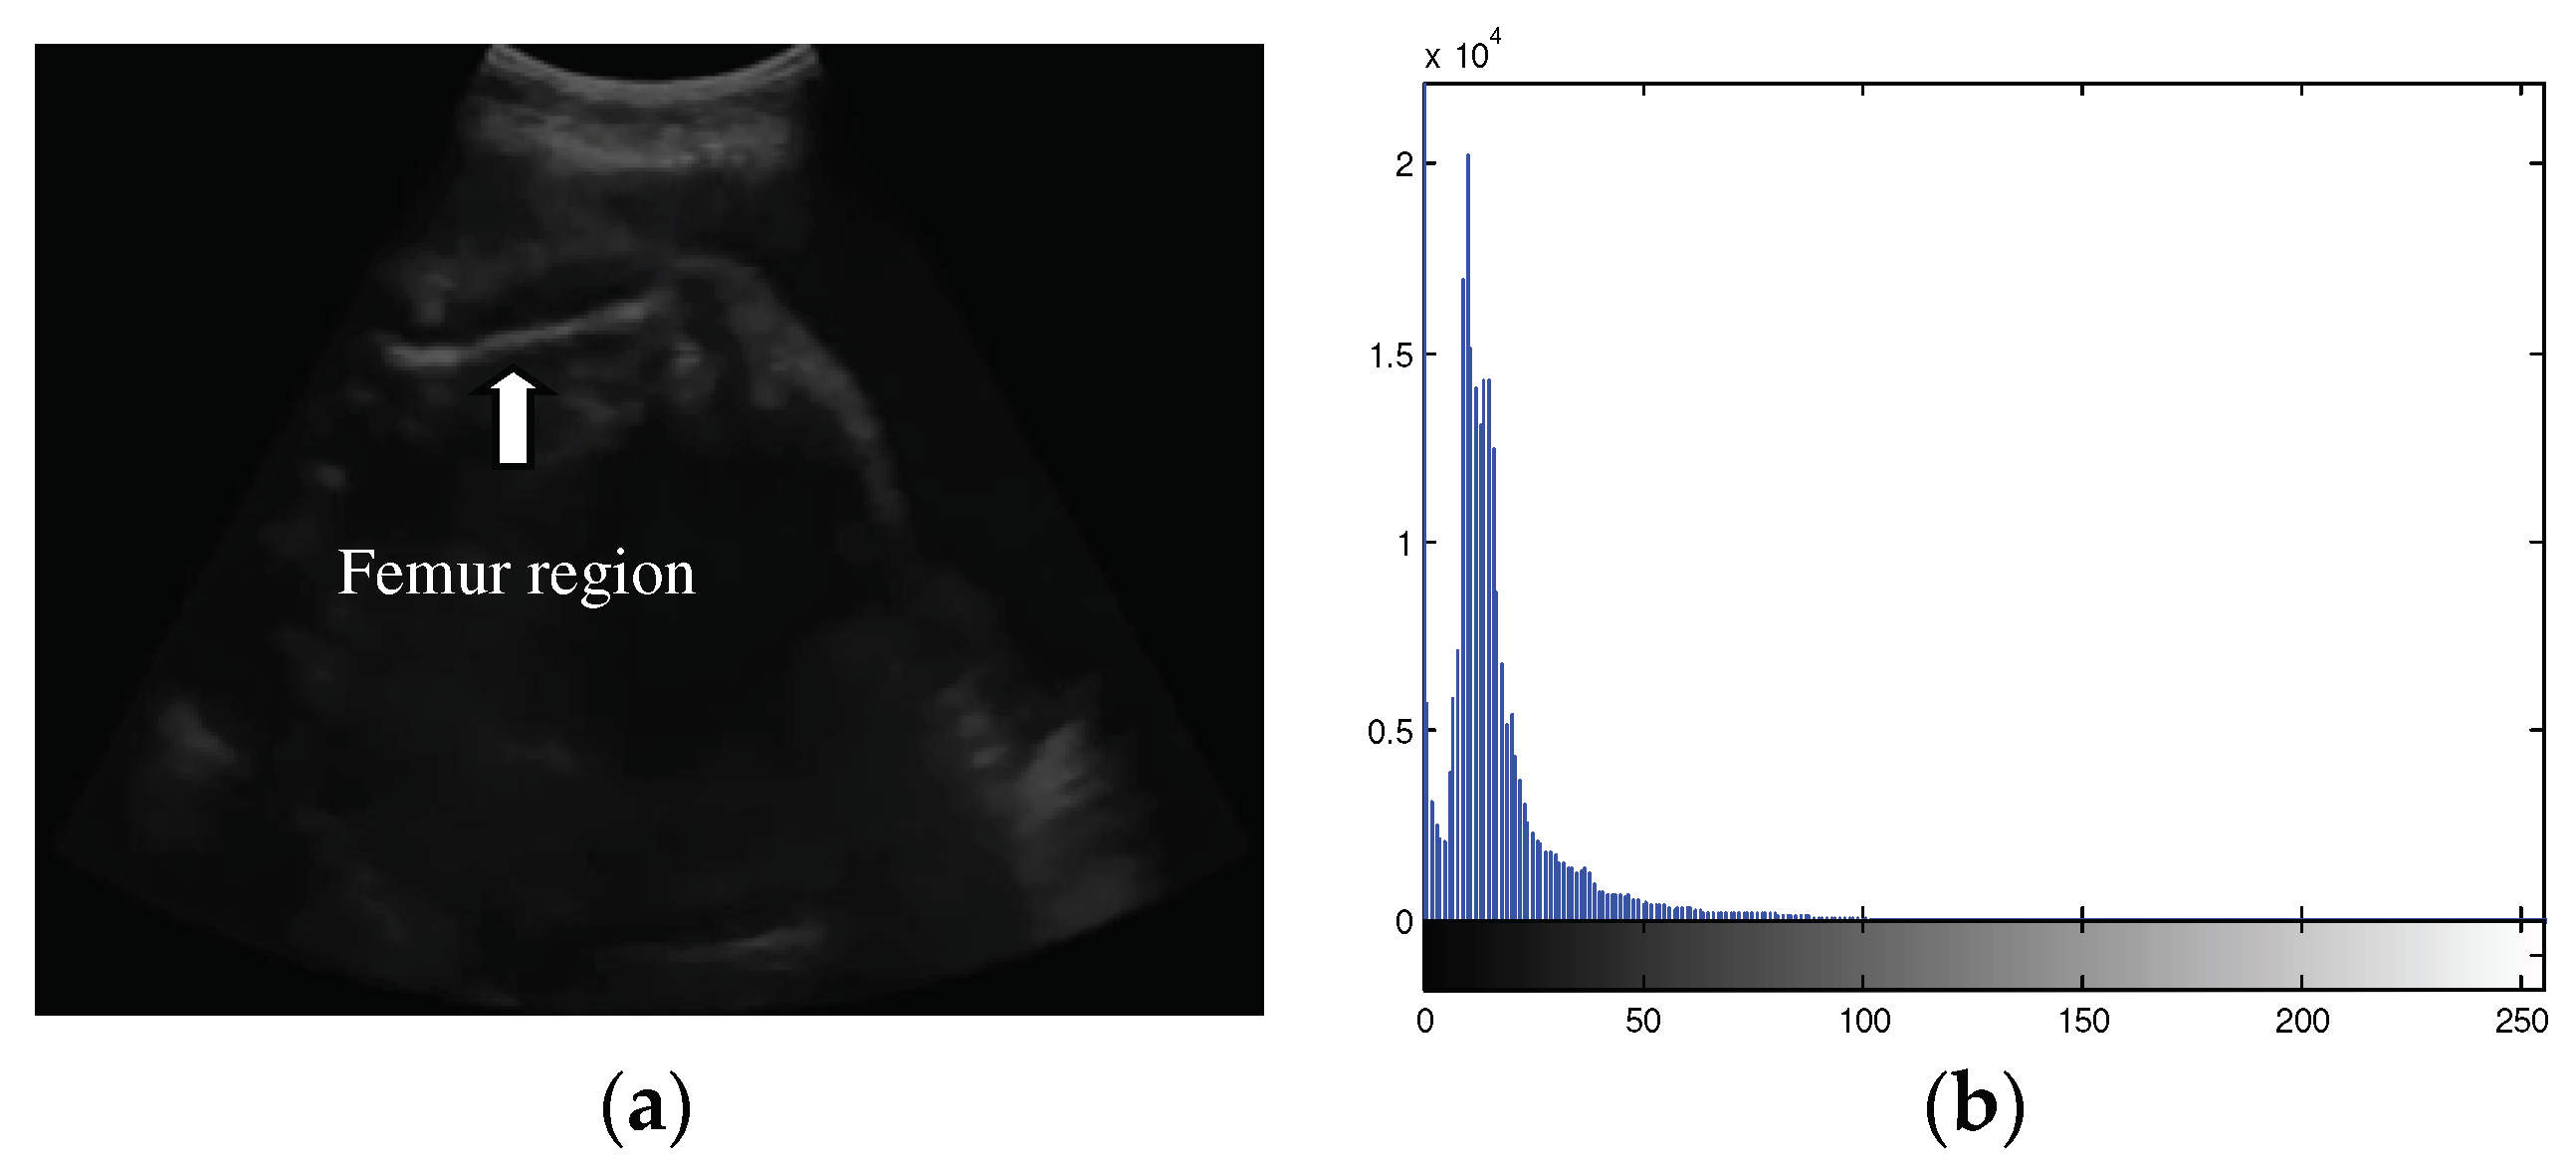

Ultrasound images used for automatic FL segmentation and measurement were collected from pregnant women with gestational ages of 15-36 weeks. The image sizes employed in this study varied. The data of 31 femur images were recorded using a Sonostar™ Ubox-10 ultrasound scanner by a midwife in Indonesia. The ultrasound images example used in the segmentation experiment are shown in Figure 2, with properties that presented in Table 1. All sample ultrasound images have a low quality and a small region of interest. The femur area indicated by the red circle in each image has a varying position and orientation. In all cases in Table 1, the femur exhibits an inclination that forms a diagonal line.

Figure 2. Example of femur ultrasound images for segmentation experiment.